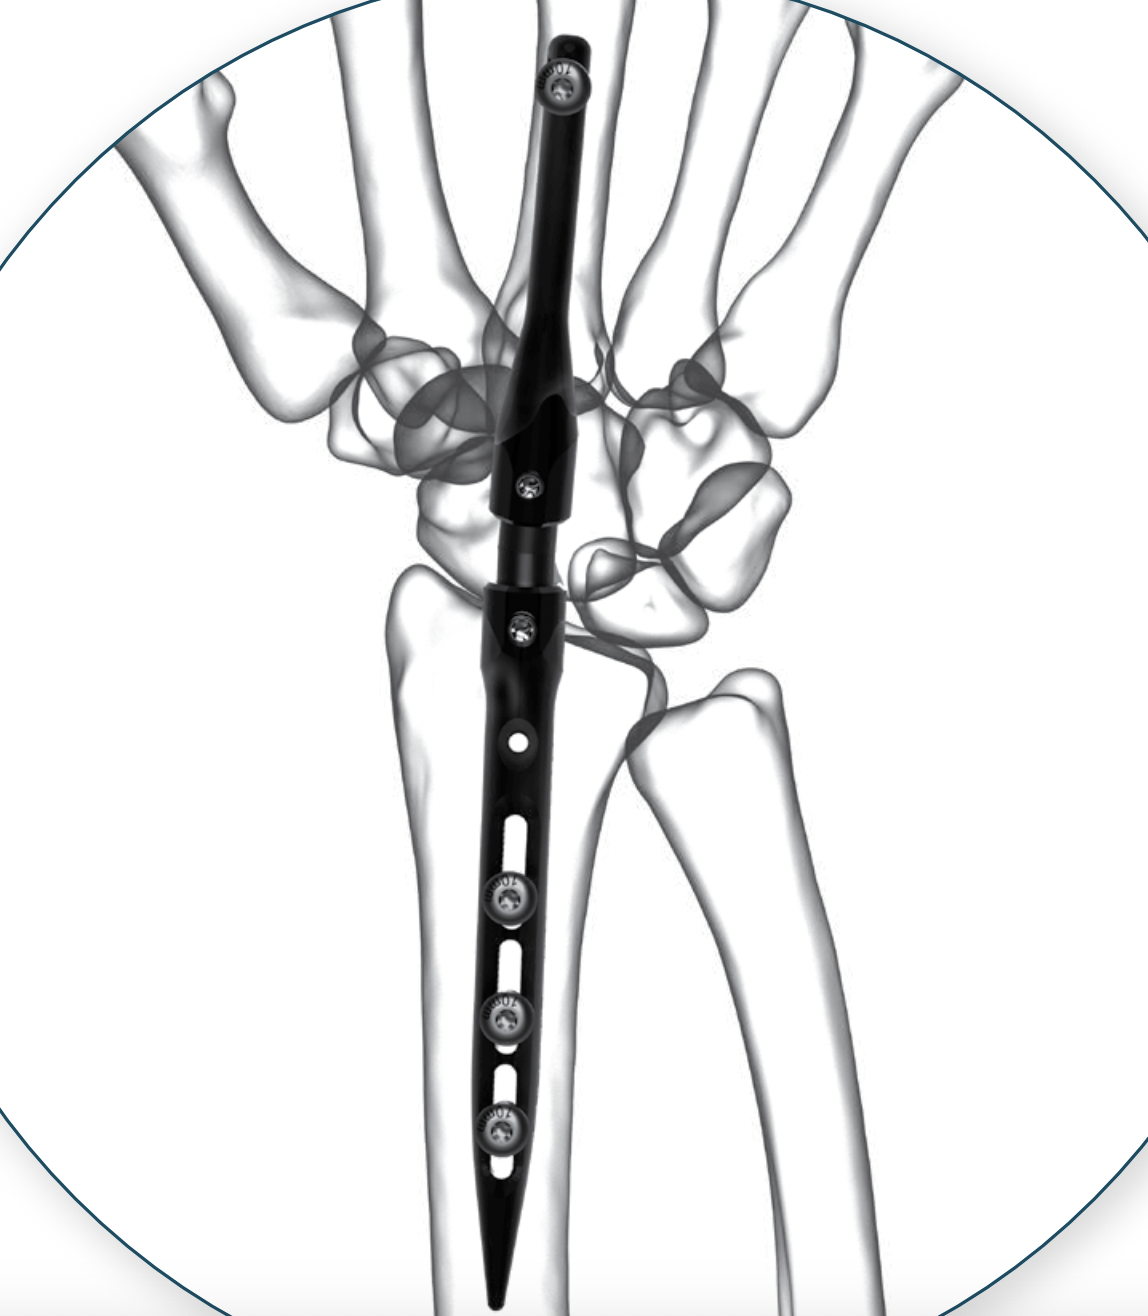

Intramedullary wrist arthrodesis

Concept

Intramedullar rod in distal radius

Intramedullary rod in 3rd metacarpal

Connected in middle with varying angles

Technique

Implate wrist arthrodesis nail

Implate wrist arthrodesis nail surgical technique

Results

Heifner et al J Wrist Surg 2023

- 32 wrist arthrodesis with locking IM nail

- union 94%

- 22% distal screw loosening

- 9% revision surgery (2/3 implant removal)